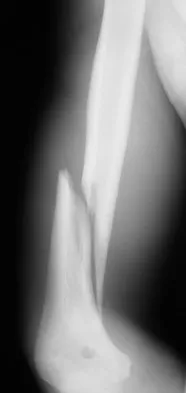

Question 34

A 35-year-old man sustained the closed injury shown in Figure 52 in his dominant extremity. Neurologic function is normal. Treatment should consist of

Explanation